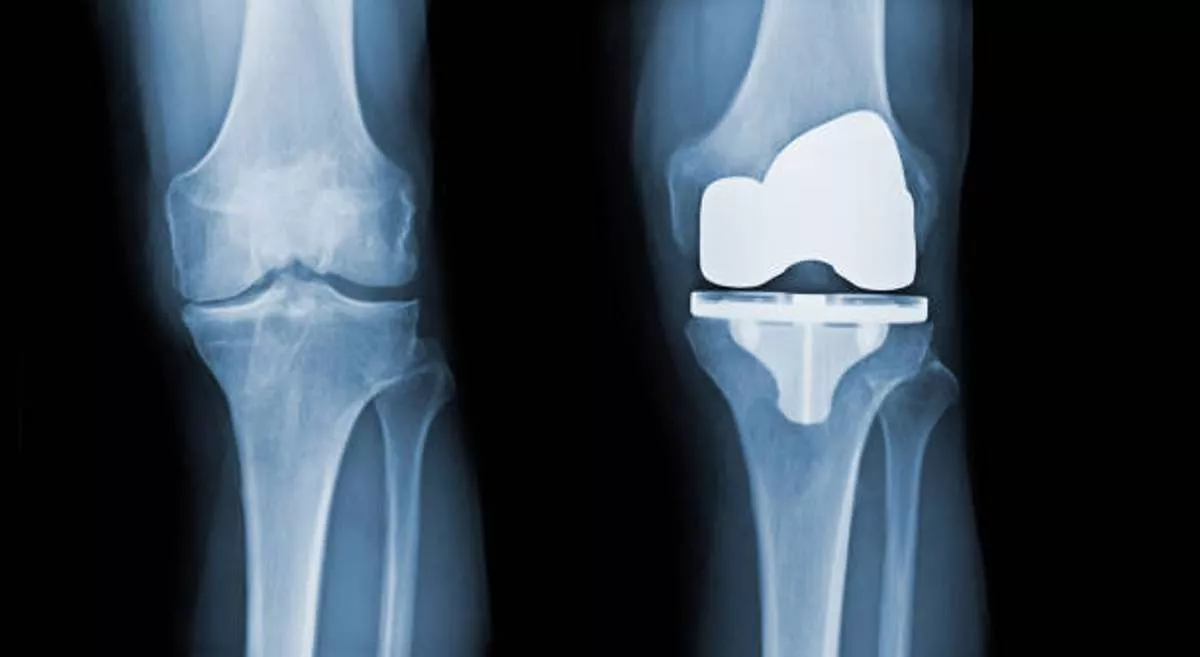

Knee Replacement Surgery, also known as knee arthroplasty, is a specialized orthopedic procedure where a damaged or arthritic knee joint is replaced with an artificial implant (prosthesis). This surgery is recommended when chronic knee pain, stiffness, or joint dysfunction no longer respond to non-surgical treatments such as medication, physiotherapy, or lifestyle changes. At Vedant Hospital, Gota, Dr. Amish Shah offers advanced knee replacement solutions for patients suffering from conditions like osteoarthritis, rheumatoid arthritis, or post-traumatic joint damage.

• Advanced joint damage – X-rays or MRI show significant cartilage loss or joint deformity.